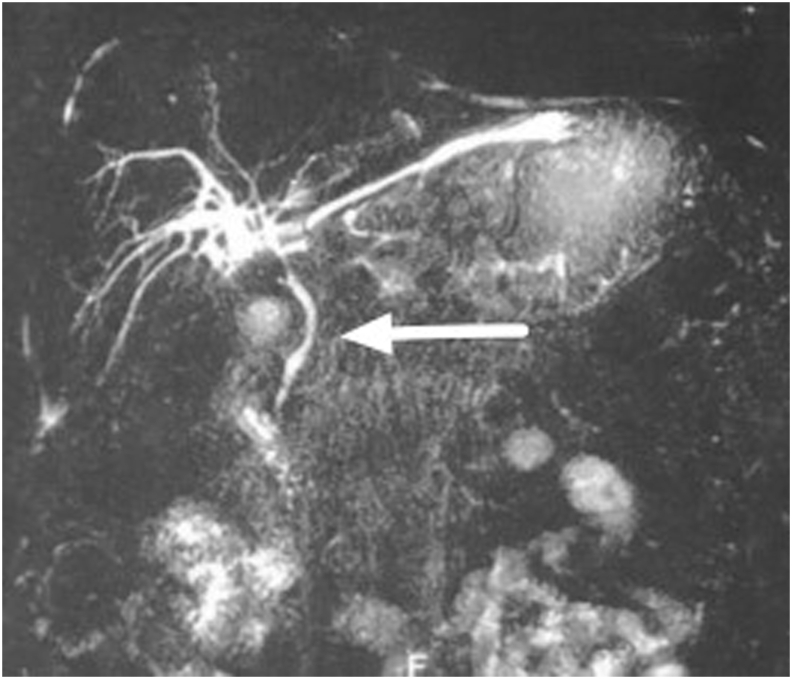

The physical examination found mild jaundice and a spongy mass in the epigastric area. Laboratory examination was conducted with the results: Hb 15.6, Leukocyte 8.76, Total Bilirubin 1.5, direct bilirubin 0.86, SGOT 103, and SGPT 427. A large epigastric cystic mass, without signs of CBD injury could be seen in the Magnetic Resonance Cholangiopancreatography (MRCP). The patient underwent multi slice computed tomography (MSCT) which revealed a cystic mass in the patient’s epigastrium, without discontinuity in CBD (see Fig. 1, Fig. 2, Fig. 3, Fig. 4).

Our patient underwent MRCP that found a large epigastric cystic mass full of leaking bile, without any signs of CBD injury. Abdominal imaging, such as abdominal ultrasound (US), multi-slice computed tomography (MSCT), magnetic resonance cholangiopancreatography (MRCP), and Chole-scintigraphy using 99mTc hepatobiliary iminodiacetic acid (HIDA) scan, are crucial to identify biloma and rule out other possible etiologies [ref. 10]. Ultrasound (US) is preferable as the first-level imaging method, since it is non-invasive, fast and easy to perform. US findings suggest biloma are a hypo-anechoic fluid collection, with well-defined margins, sometimes encapsulated, mono- or pluriconcamerate appearance, in a typical location (right upper abdominal quadrant: sub- or intrahepatic, below the diaphragm) and no vascularity on color Doppler US. The size of a biloma may vary from a few centimeters up to 40 cm in diameter. But the sensitivity of abdominal US is low (70%), though it is used as the initial imaging in the evaluation of biloma. The sensitivity and specificity of CT scan are approximately 90% and those of MRI are above 95% in the detection of biloma and bile leak; however, smaller bilomas can be missed [ref. 4,ref. 10]. The MRCP sequences are helpful to identify the source of the biliary leak. Specifically, thin-slab MRCP sequences may show the point of communication between the fluid collection and bile ducts. Thin-slab MRCP sequences are also helpful in depicting the detailed anatomy of the biliary system and in detecting accessory biliary ducts, which could potentially be the source of the bile leak [ref. 9,ref. 11].